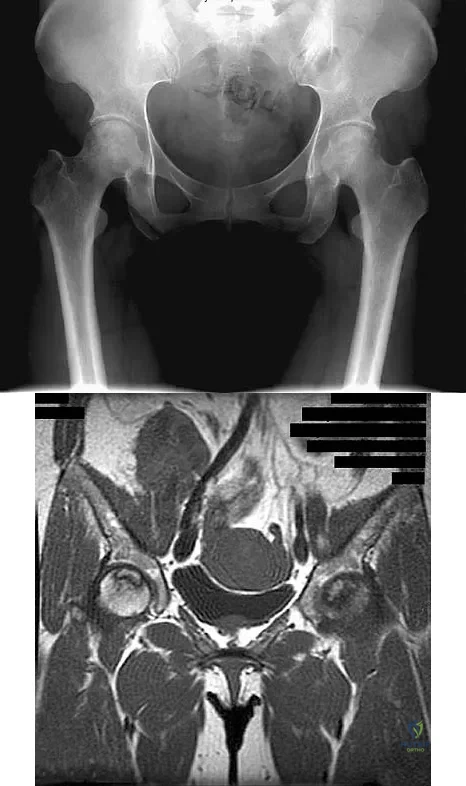

Figure 41 shows the MRI scan of a 39-year-old man who has severe left groin and anterior thigh pain. What is the most likely diagnosis?

Explanation

A 46-year-old woman has bilateral groin pain, with more severe pain on the left side than on the right side. Figures 44a and 44b show a radiograph and a T1-weighted MRI scan. What is the most likely diagnosis?

Explanation